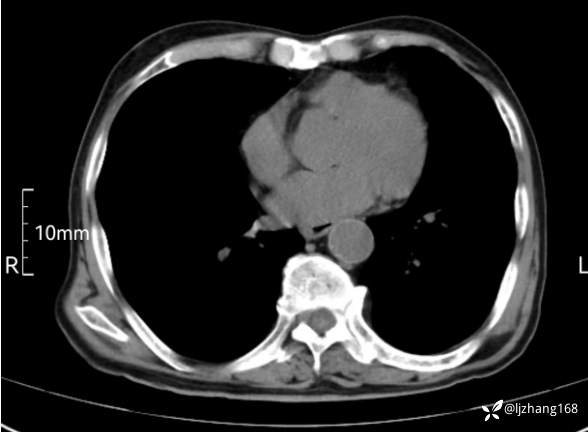

辅助检查:胸部CT:双肺肺气肿,间质性病变,血气分析:PH 7.413, PCO2 29.2mmHg, PO2,81.8mmHg,乳酸 3.3mmol/1,剩余碱-4.0mmol/1,HC03 18.8mmol/1。全血超敏C反应蛋白:超敏C反应蛋白 135.60 mg/L、 白细胞 14x19^9/L,中性粒细胞11.6x10^9/L。